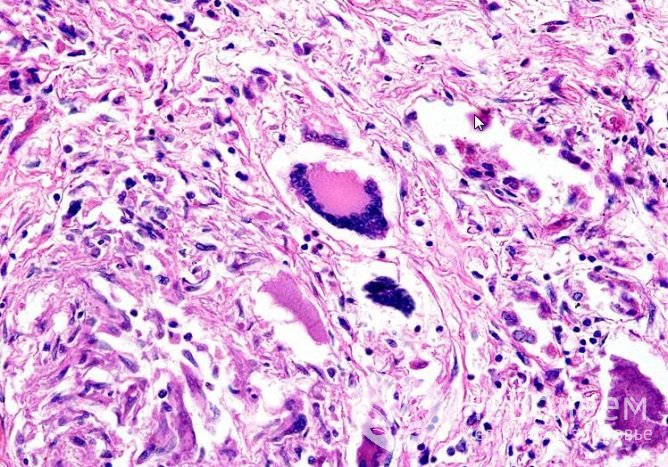

При гранулематозе Вегенера иммунные клетки атакуют стенки сосудов и окружающую тканьИммунная система, определяя собственную ткань как чужеродную, вырабатывает к ней антитела. Антитела повреждают стенки кровеносных сосудов, что влечет образование участков воспаления, то есть гранулем. Постепенно увеличиваясь в размере, гранулемы закрывают просвет сосуда. В итоге нарушаются кровоснабжение тканей, процессы тканевого дыхания и метаболизма.

Гранулематоз Вегенера – аутоиммунное гранулематозное воспаление стенок сосудов (васкулит)Точные причины возникновения гранулематоза Вегенера неизвестны. Учитывая, что в крови при рассматриваемом заболевании обнаруживаются иммунные комплексы, его относят к аутоиммунным патологиям. Предположительно, болезнь развивается в результате ошибки иммунной системы, вследствие которой ткани сосудистых стенок воспринимаются иммунной системой как чужеродные и подлежат разрушению. К этому могут привести различные воспалительные процессы, в том числе инфекционные.